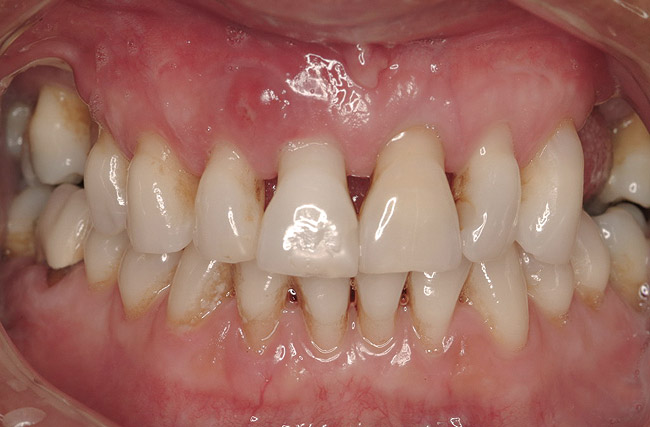

A 46-year-old woman presented with advanced chronic periodontitis and had already lost several maxillary and mandibular teeth (Figure 13 and Figure 14). She initially complained of pain in the maxillary anterior sextant, where a draining sinus tract between tooth Nos. 7 and 8 was evident. The patient desired a fixed restoration and was unwilling to wear a removable prosthesis, even on a temporary basis, if possible. It was decided that tooth Nos. 2, 6, 11, and 15 would be retained to support a fixed, provisional bridge, while the patient’s remaining teeth would be extracted and bone augmentation performed, followed by implant placement (Figure 15). Extraction of the maxillary teeth with the exception of these four teeth was done to simplify provisionalization.

Figure 14  Severe periodontitis and periodontal abscess on the facial aspect of tooth Nos. 7 and 8. All maxillary teeth were hypermobile and the patient was symptomatic in the anterior sextant.

Figure 14